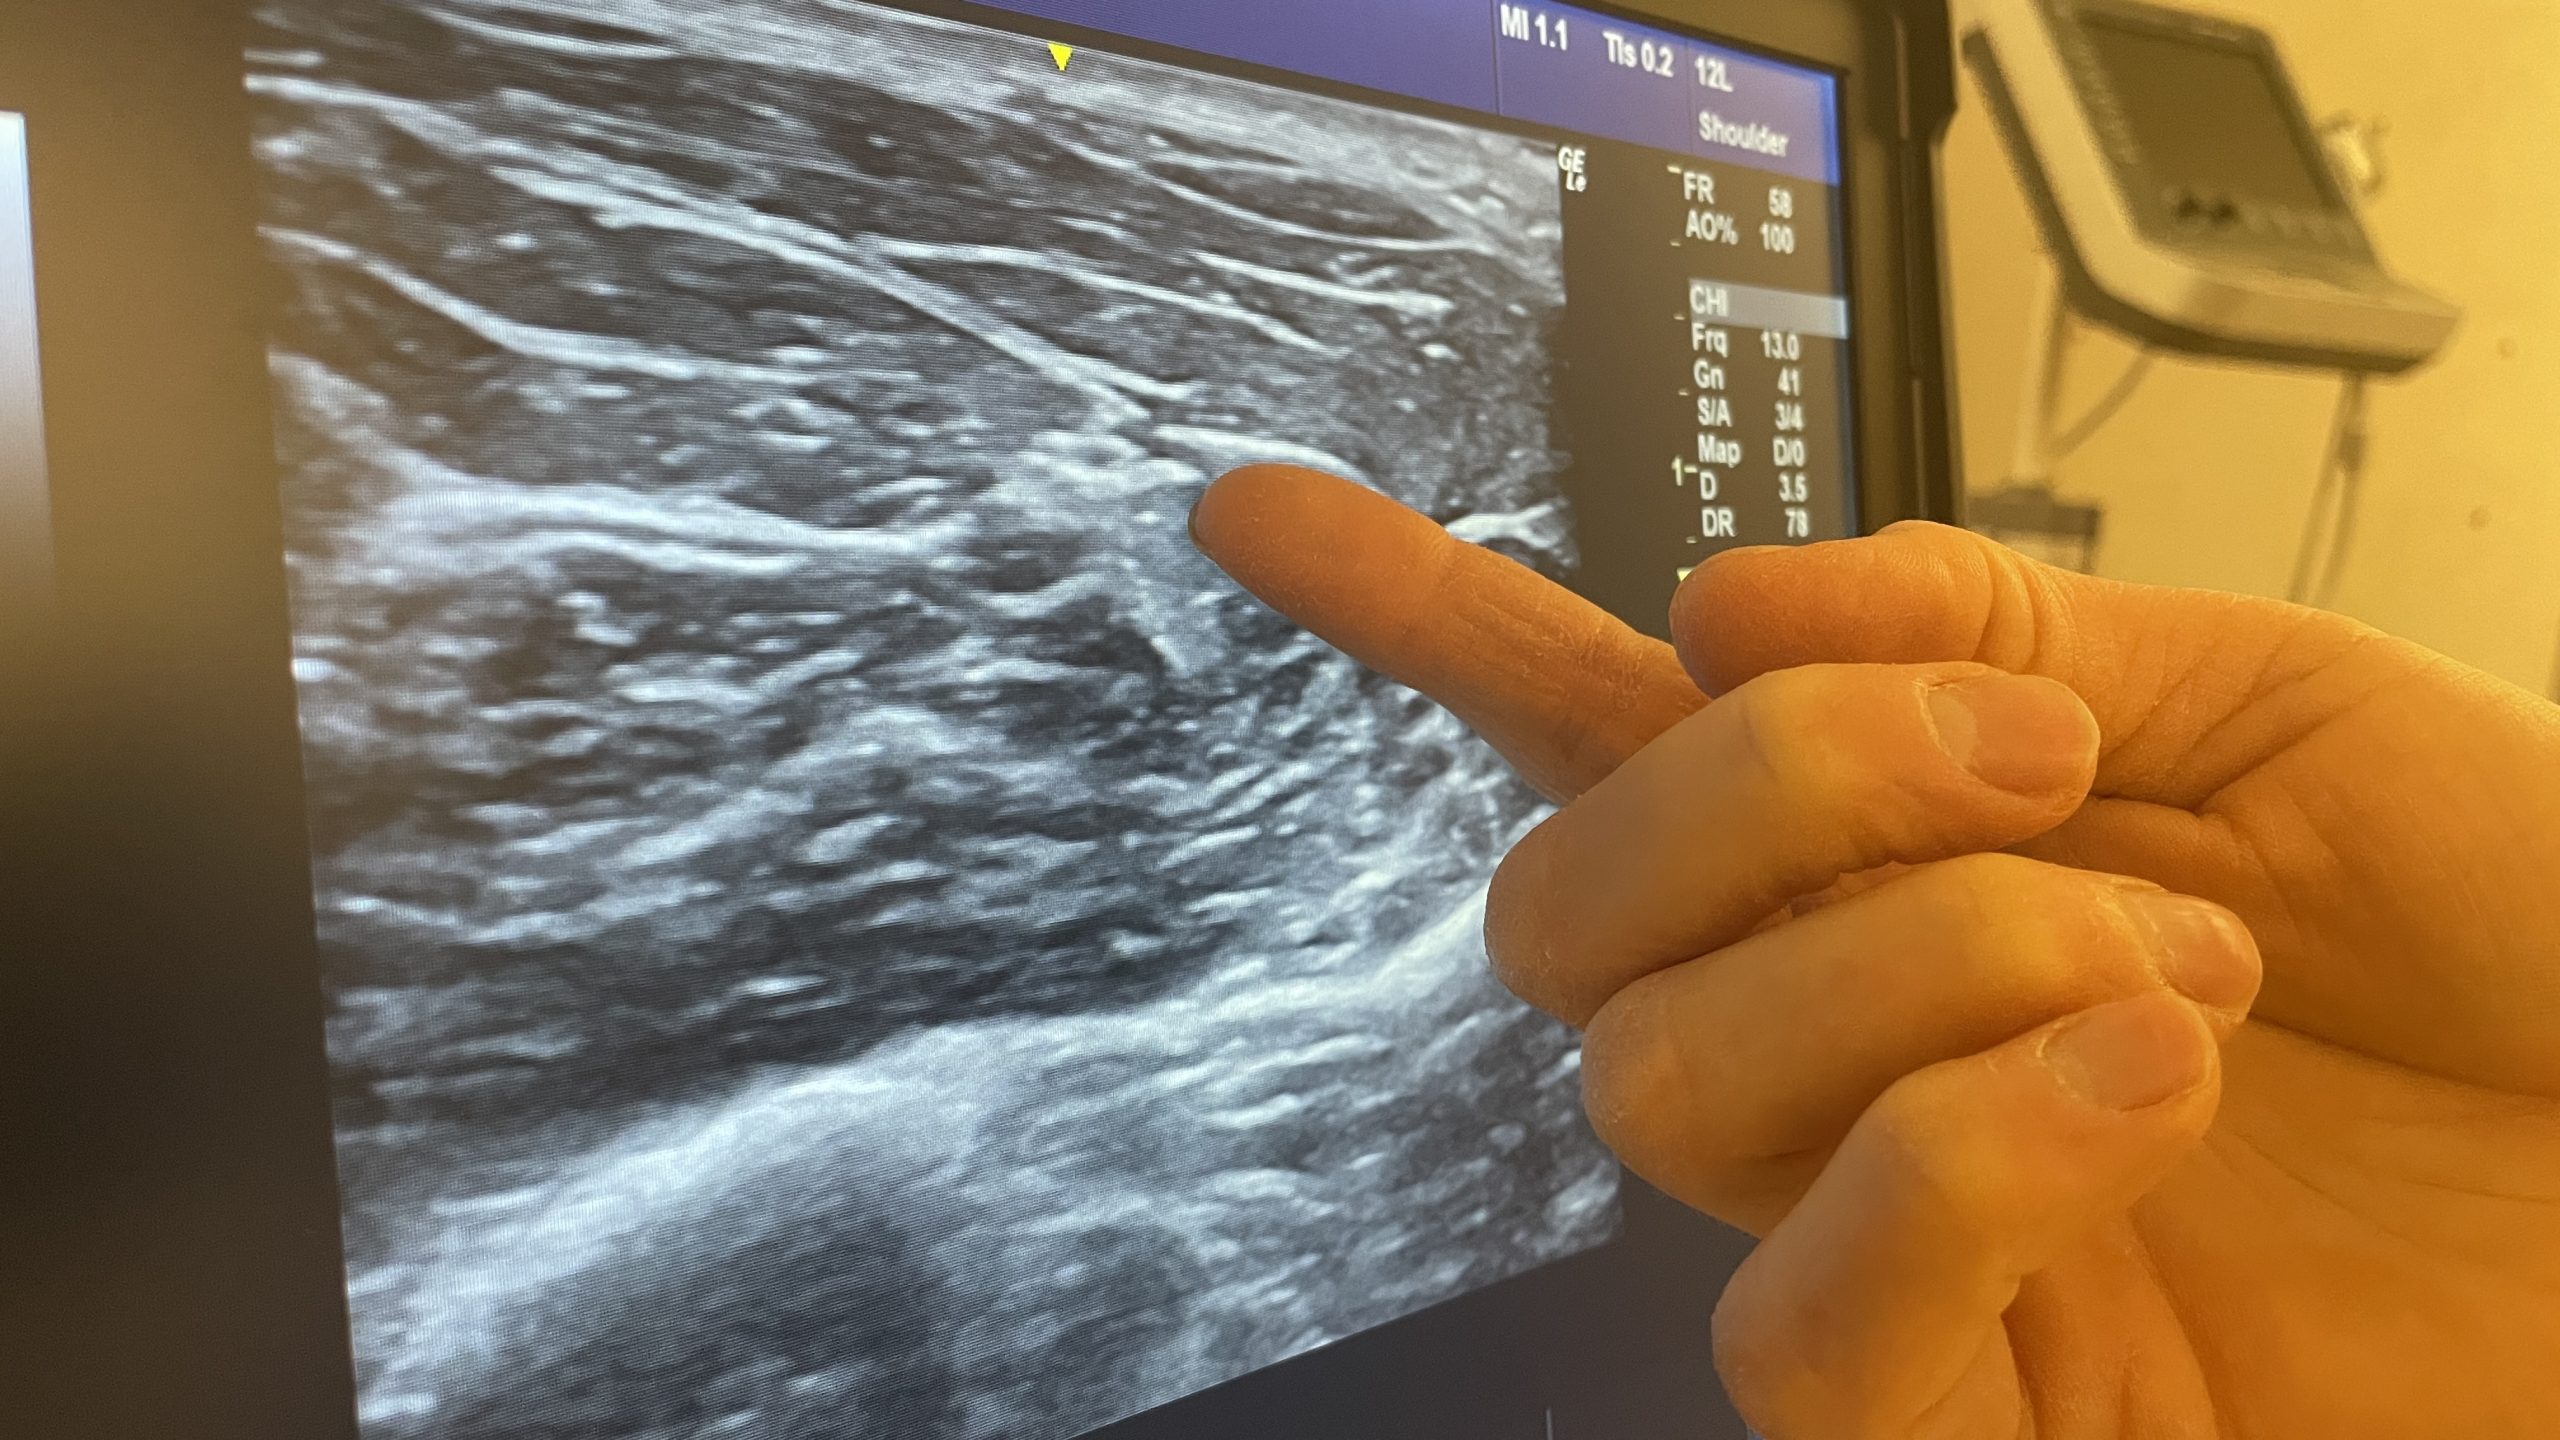

Hur Fungerar Ultraljud . Med ultraljud kan man få fram rörliga. alla organ och vävnader i kroppen som innehåller mycket vatten kan undersökas med ultraljud. med hjälp av ultraljud går det att undersöka många av kroppens vävnader och organ, som till exempel hjärtat, gallblåsan, blodkärlen. ultraljud av hjärtat, även kallat ekokardiografi eller ucg, är en medicinsk bildteknik som används för att undersöka. ultraljud är ljud som har så ljus ton att människans öra inte kan uppfatta det. medicinskt ultraljud eller sonografi är en ultraljudsbaserad bilddiagnostisk undersökningsmetod.